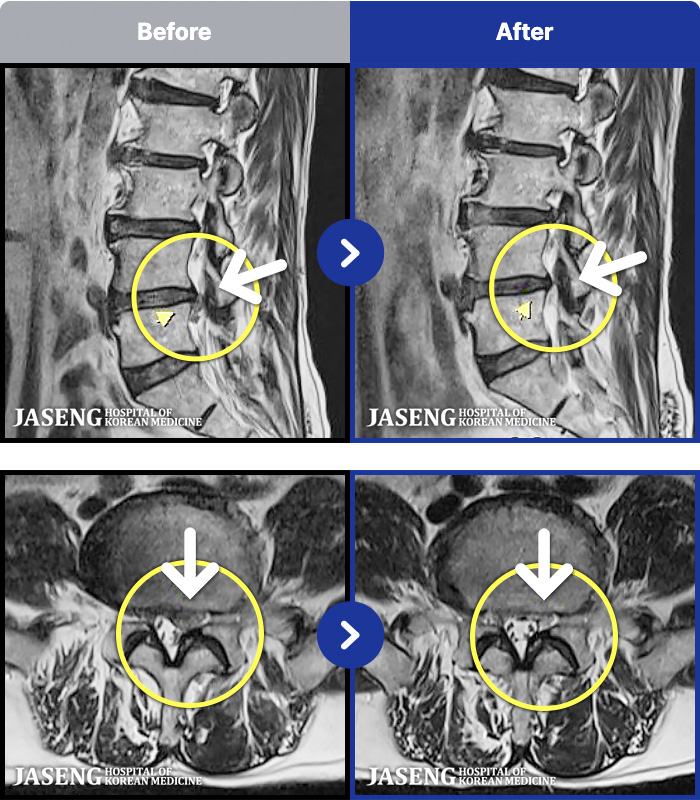

1,237 MRI ũ ʸ Ȯϼ.

1,237